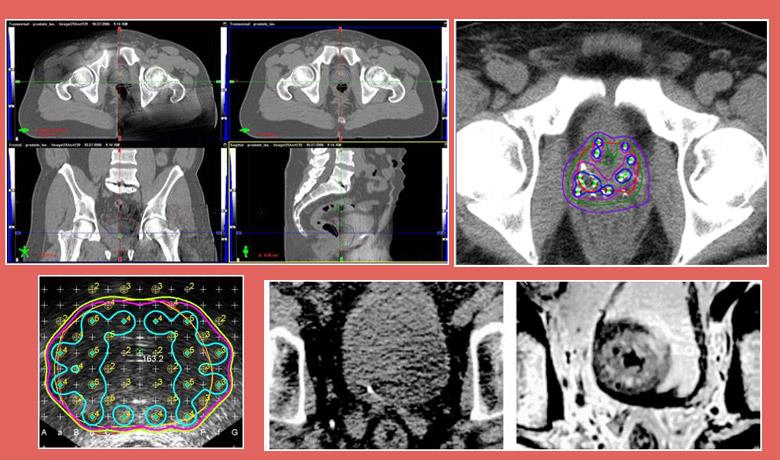

External beam radiation therapy uses high-energy X-rays (photons) to treat prostate cancer. The rays are produced by a linear accelerator, positioned at a distance from the patient’s body. Three Dimensional Conformal Radiotherapy (3D-CRT) is the most frequently used external beam radiation therapy technique, while Intensity Modulated Radiotherapy (IMRT), an improved version of 3D-CRT which focuses the dose on the target and avoids healthy tissues, has been increasingly gaining ground over recent years, especially in terms of treating prostate cancer.

Brachytherapy is a form of radiation therapy in which a radioactive source irradiates the prostate from the inside. This can be achieved using two techniques. Either with permanent seed implantation (radioisotopes) in the prostate gland that cease irradiating 9-12 months after implantation into the patient’s body (LDR – Low Dose Rate Brachytherapy), or with the temporary placement of catheters, which are removed once treatment is completed (HDR – High Dose Rate Brachytherapy).

- IMRT allows radiation oncologists to increase the dose being delivered to the prostate up to 86 Gy, while protecting neighboring healthy tissues. This is the only technique that allows the safe increase of the dose beyond 76 Gy with conventional fractionation or the increase of the dose with subfractionation (larger daily radiation doses).

- Moreover, IMRT allows the delivery of high doses to clinically suspicious pelvic lymph nodes, while protecting the small intestine.

- Fusion of CT planning images with MRI or MRI Spectroscopy images